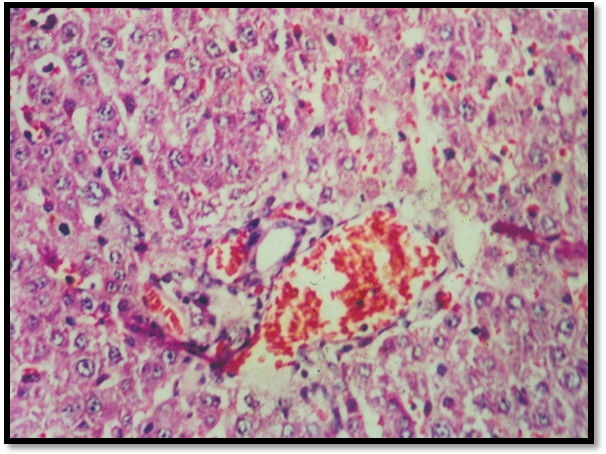

Histopathological observations

Histopathology of normal rat liver revealed prominent central view, normal arrangement of hepatic cells (Fig. 7). Microscopic examination of CCl4 treated liver section shows necrosis and fatty degeneration (Fig. 8). Liver section treated from Silymarin protected the structural integrity of hepatocyte cell membrane and recovery of hepatocyte cells (Fig. 9). Scopoletin treated group showed maximum recovery of hepatocytes, no fatty degeneration and necrosis and exhibited significant protection against CCl4 induced liver toxicity in rats (Fig. 10).

Photomicrographs of liver tissues of different groups of Albino rats

Fig. 10: Scopeletin treated group